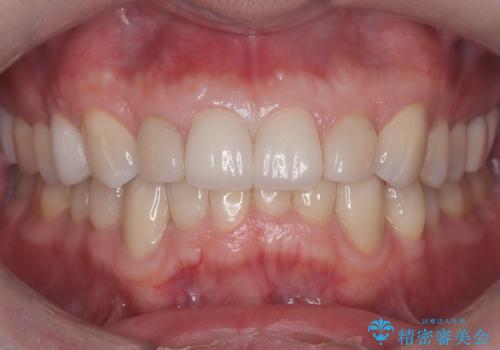

メタルインレーからセラミックインレーへ

セラミックインレーに治療を行っております。

e-max プレスインレーにて修復治療を行っているため適合性及び審美性の高い治療を行うことができます